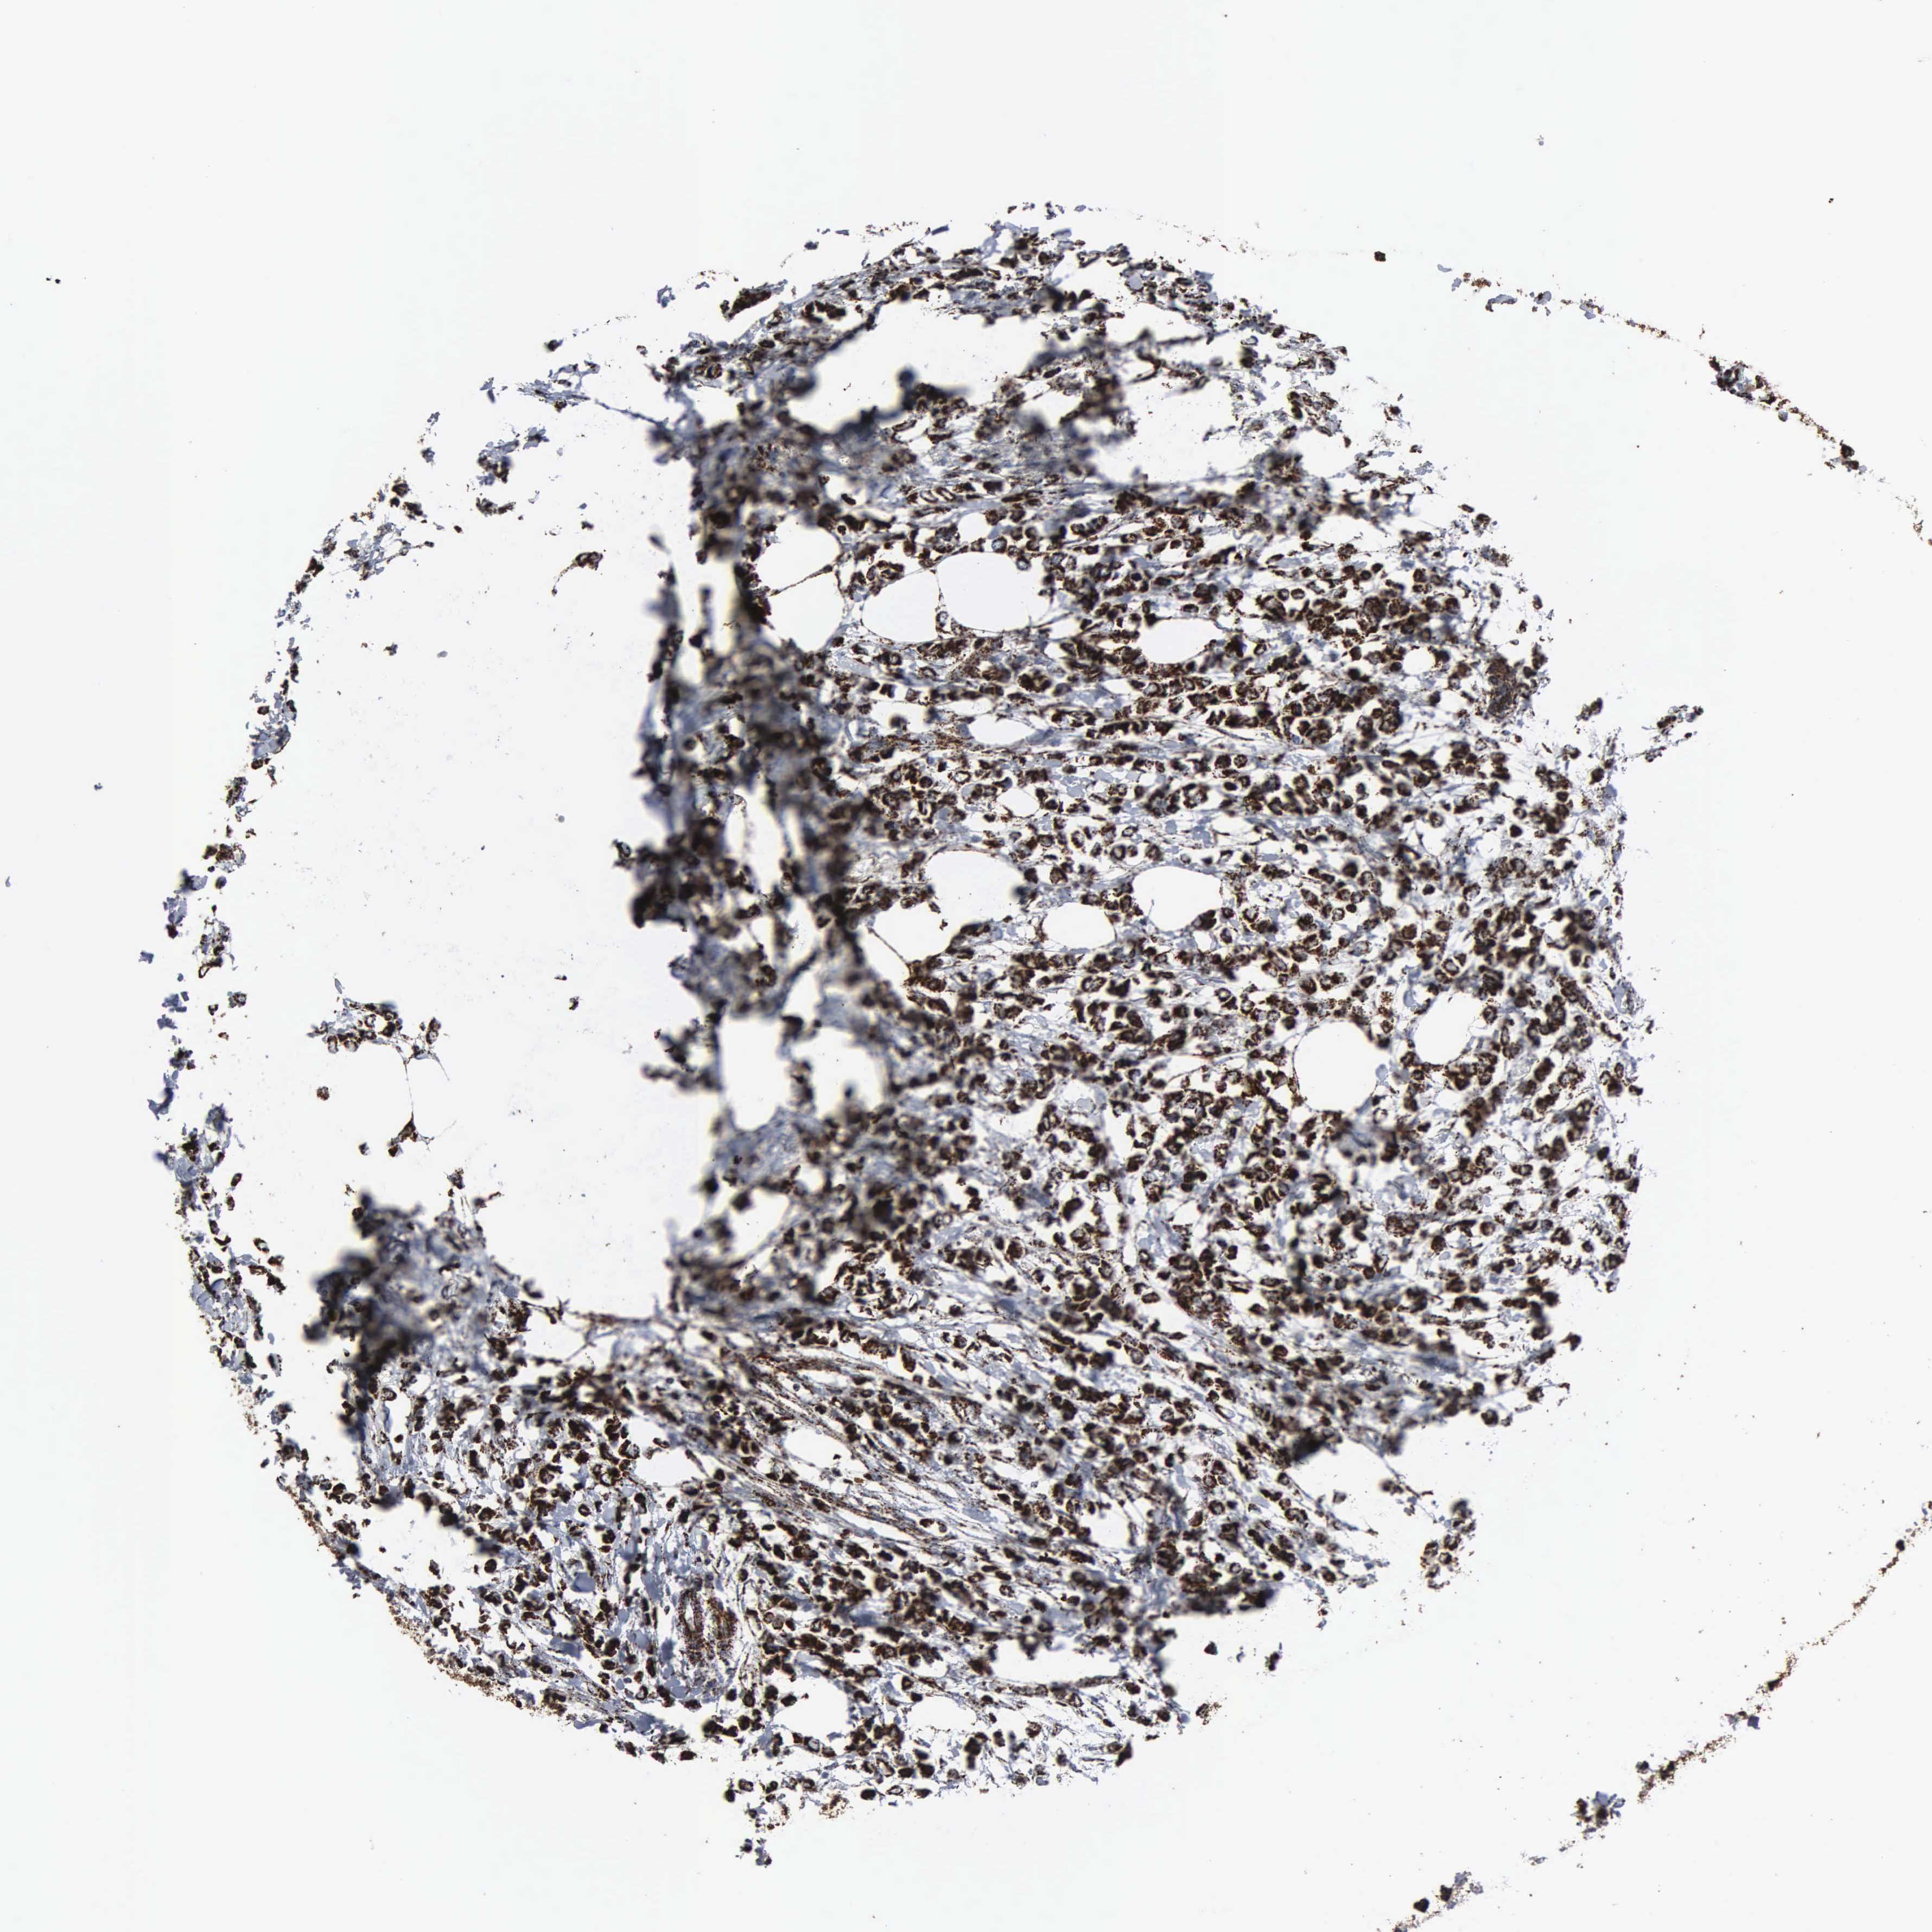

BRCA TCGA BRCA VALIDATION PROTEIN EXPRESSION

Breast cancer

Human cancer